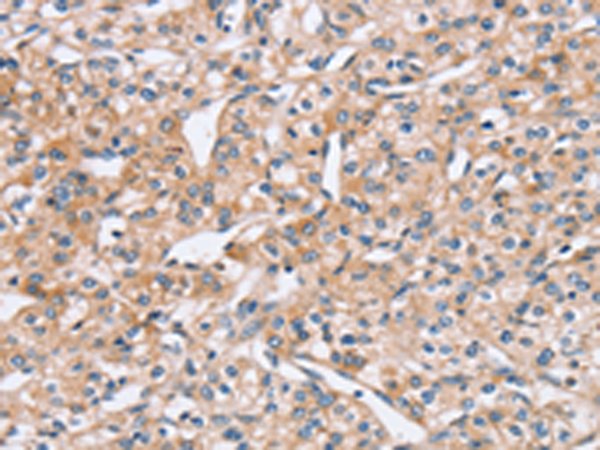

分类: 科研抗体货号: P08611别名: PED; MAT1; HMAT1; MAT1H; PEA-15; HUMMAT1H应用: IHC反应种属: Human, Mouse, Rat